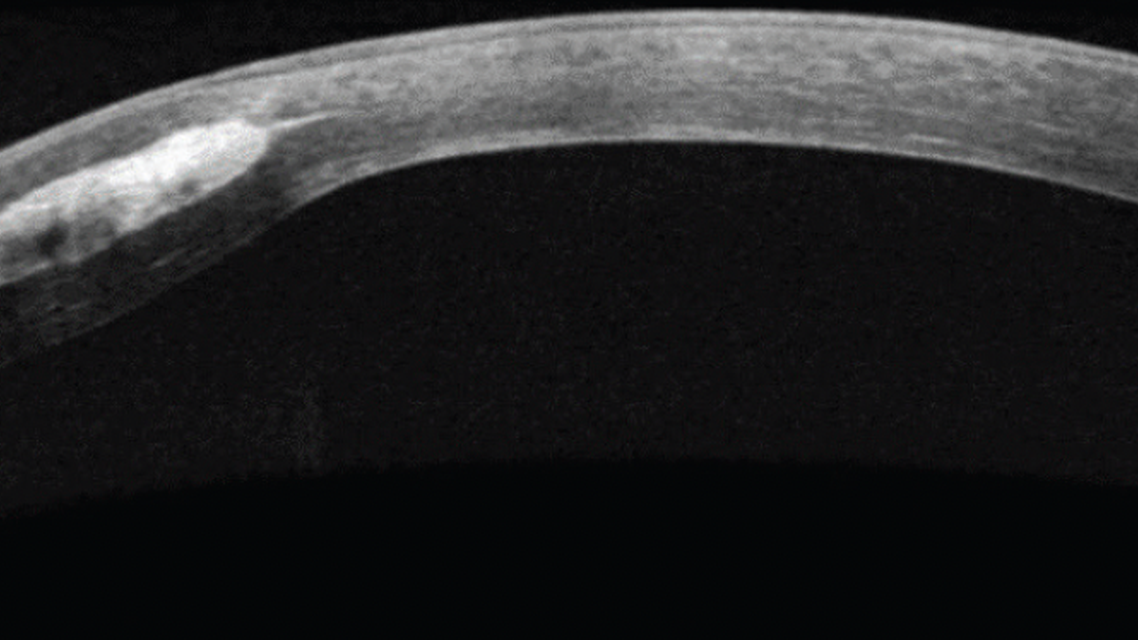

Although polymethyl methacrylate rings are still used as ICRSs, corneal allogenic intrastromal ring segments (CAIRS) have recently been used to enhance visual outcomes post-CXL.12,17 CAIRS uses allogenic donor tissue cut into segments that are implanted within the stroma, resulting in corneal flattening and regularization. The primary treatment purpose is to improve spectacle-corrected and UCVA in patients with keratoconus. Unlike Intacs Corneal Implants (Addition Technology), CAIRS can be implanted more anteriorly within the stroma, which may produce higher potency in reducing anterior corneal irregularity (Figures 1 and 2).12 Additionally, allogenic grafts have presumably reduced complication risks when compared with synthetic material. To date, there have been no reports of corneal melts, foreign body sensation, halo or glare effects, or allograft rejections.13

A 28-year-old male with keratoconus presented to the Midwestern University Eye Institute for a TG-PRK evaluation of each eye with complaints of poor, variable vision OU. He had already undergone epi-off CXL OU 3 years prior (Figure 2). Per the patient, given his difficulty inserting and removing scleral lenses and with lens fit and comfort with corneal gas permeable lenses, he was informed that corneal transplants might be the next best management option. His ultimate goal was to improve his vision enough to go through school. He reported a loss of ability to read, which he required to successfully complete his education.

The patient’s entering UCVA was 20/125 OD and 20/200 OS. After evaluation, it was determined that he was not a good candidate for TG-PRK, and alternative surgical options were reviewed with him. He elected to pursue CAIRS OD and toric ICL OS.

One month later, the patient was less satisfied with his vision OS, and CAIRS OS was subsequently recommended. Upon healing from the CAIRS and ICL procedures (Figure 3), his UCVA improved to 20/80+ OD and 20/40-2 OS, allowing him more functional vision without lens wear. Encouraged by the clinical results, he was open to being refit in scleral lenses to further refine his vision. He was first refit into a scleral lens OD 1 month after CAIRS implantation, which yielded BCVA of 20/20. With improved UCVA OU and BCVA OD, he is looking forward to a scleral lens refit OS at his next CAIRS follow-up appointment.